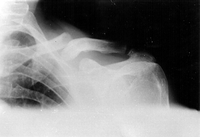

Clavicle fracture

Anteroposterior radiograph of right shoulder demonstrating clavicle fracture

Arnold S et al. BMJ Case Reports CP 2021;14:e241382; used with permission